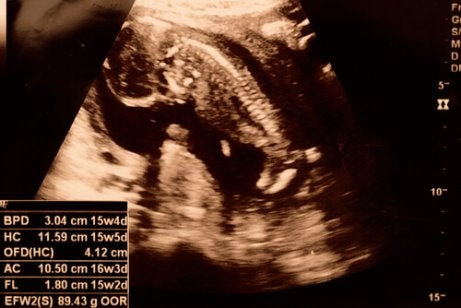

På vissa ultraljudsbilder är det möjligt att bestämma barnets kön så tidigt som vid 15 veckor. Fostrets armar och ben växer och det kan böja sina leder.